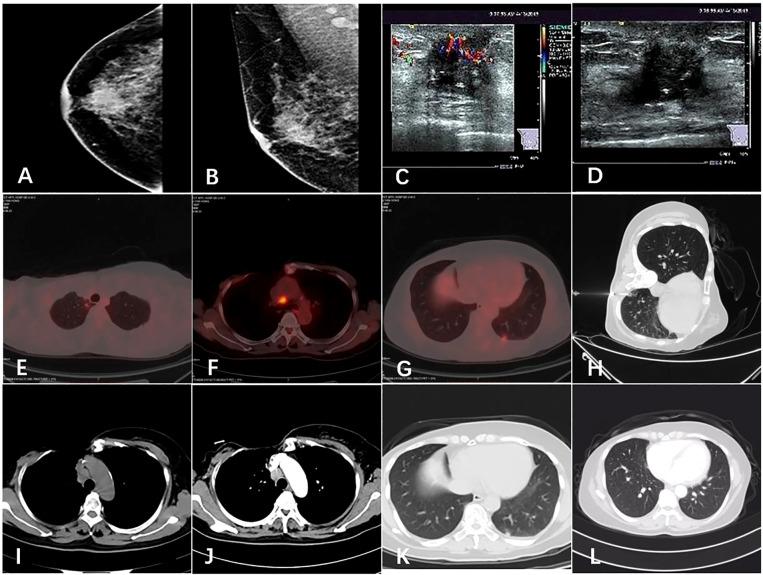

Primary squamous cell carcinoma (PSCC) of the breast, as a rare metaplastic breast cancer, currently has limited clinical data on its biological behavior, treatment and prognosis. At present, the optimal treatment of this tumor is still controversial. We reported a case of a 56-year-old woman with a mass on the right breast. She underwent a modified radical mastectomy and lymph node biopsy, which revealed that the tumor was a metaplastic squamous cell carcinoma with axillary lymph node metastasis, followed by traditional adjuvant chemotherapy and radiotherapy. The patient re-examined by PET/CT after two years in May 2017 and found a recurrence in the right chest wall, so resection of the recurring lesion was resected, then she was given postoperative adjuvant radiotherapy and chemotherapy. In August 2019, the patient re-examined by PET/CT, and there were pulmonary and mediastinal lymph node metastases. After 4 cycles of albumin paclitaxel plus cisplatin chemotherapy combined with nivolumab immunotherapy, the patient achieved complete response (CR), and then switched to nivolumab immune maintenance therapy. So far, no obvious metastasis has been seen. We believe that surgical treatment is necessary for PSCC of the breast;paclitaxel and cisplatin chemotherapy regimens and adjuvant radiotherapy are effective, but it may be resistant to radiotherapy; and immunotherapy may prolong the survival of patients with PSCC of the breast.

乳腺原发性鳞状细胞癌(PSCC)作为一种罕见的乳腺化生性癌,目前关于其生物学行为、治疗及预后的临床数据有限。目前,该肿瘤的最佳治疗方案仍存在争议。我们报告了一例56岁右乳肿物的女性患者。她接受了改良根治性乳房切除术及淋巴结活检,结果显示肿瘤为伴有腋窝淋巴结转移的化生性鳞状细胞癌,随后接受了传统辅助化疗和放疗。2017年5月患者在两年后接受PET/CT复查,发现右胸壁复发,遂切除复发病灶,之后给予术后辅助放疗和化疗。2019年8月,患者接受PET/CT复查,出现肺及纵隔淋巴结转移。在接受4周期白蛋白紫杉醇联合顺铂化疗并联合纳武单抗免疫治疗后,患者达到完全缓解(CR),随后转为纳武单抗免疫维持治疗。迄今为止,未见明显转移。我们认为,手术治疗对于乳腺PSCC是必要的;紫杉醇和顺铂化疗方案及辅助放疗是有效的,但可能对放疗耐药;免疫治疗可能延长乳腺PSCC患者的生存期。